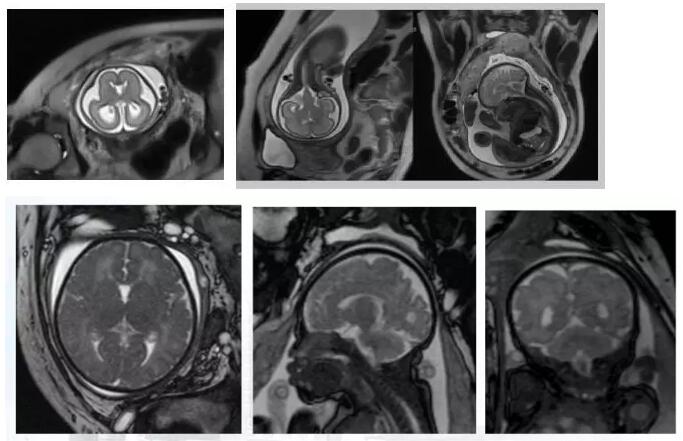

磁共振檢查不受胎兒骨骼及羊水量的影響,對(duì)胎兒中樞神經(jīng)系統(tǒng)、羊水過(guò)少、雙胎、孕周較大時(shí)顯示很好,特別是孕晚期胎頭入盆或胎兒顱骨骨化時(shí)。

磁共振圖像可以在各個(gè)方位看到寶寶的顱腦,還能看到寶寶撅起的小嘴。

磁共振圖像可以在各個(gè)方位看到寶寶的顱腦